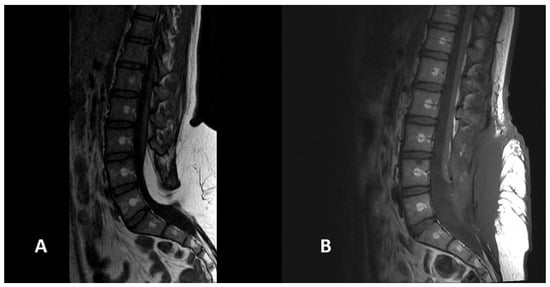

Figure 5. A preoperative (A) scan of a SCM1 with a bone spur separating two dural sacs and two hemicords (white arrow). The postoperative image (B) shows the removal of the bone spur and the reconstruction of a single dural sac.

SCM is characterised by a split, double spinal cord. It is caused by a defect in the phase of cellular migration from the epiblast to the primitive cord, a process that normally leads to cellular integration and the formation of the notochord. If integration does not occur, two notochords are formed, triggering the formation of two hemicords [4]. A distinction is made between SCM1, in which there is a bone spur between the two halves of the spinal cord, and SCM2, in which the two hemicords are separated by a fibrous membrane. SCM1 is characterised by two dural sacs, while the dural sac in SCM2 is a single one. Both forms hinder the normal ascent of the conus and the spinal cord. For this reason, it is necessary to remove the bone or membrane separating the two hemicords and create a single dural sac. In our series, SCM1 was present in three cases and SCM2 in two cases. Two patients with SCM1 were treated surgically (Figure 5), and one patient with SCM1 rejected surgical treatment. Both patients with SCM2 are asymptomatic and are under strict follow-up with annual electromyographic and urodynamic tests.